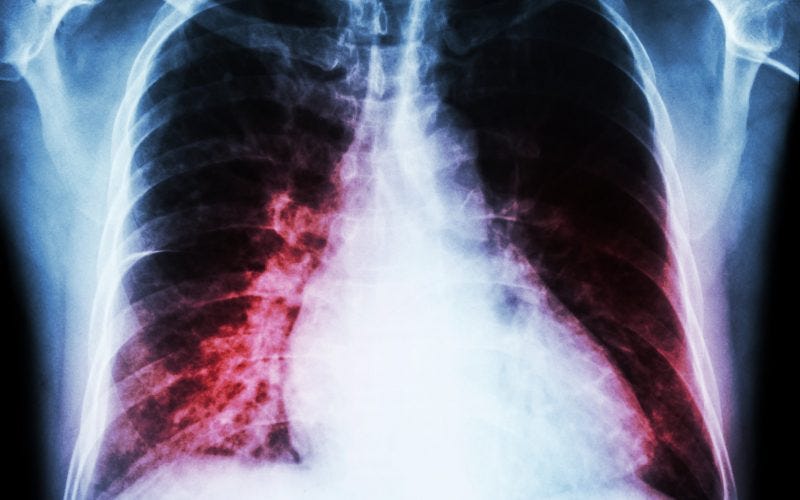

“Autopsy findings showed congestive edema of the lungs, T-cell lymphocytic and macrophage infiltration in the lungs, pericardium, and myocardium of the left atria and left ventricle, liver, kidneys, stomach, duodenum, bladder, and diaphragm. Since there was no preceding infection, allergy, or drug toxicity exposure, the patient was diagnosed with post-vaccination pneumonia, myopericarditis, hepatitis, nephritis, gastroenteritis, cystitis, and myositis. Although neither type of inflammation is fatal by itself, arrhythmia is reported to be the most common cause of death in patients with atrial myopericarditis. In the present case, arrhythmia of atrial origin was assumed as the cause of cardiac failure and death. In sudden post-vaccination deaths, aggressive autopsy systemic search and histological examination involving extensive sectioning of the heart, including the atrium, are indispensable.”